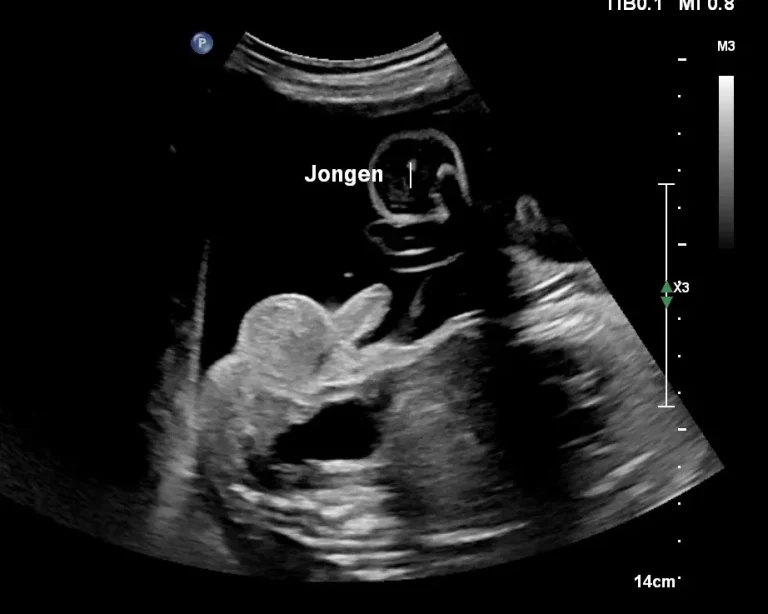

Starting at 14 weeks, we use a sex determination ultrasound to look at the gender of your baby. The preferred term is around 15-16 weeks, so you can see it a little better yourself. Because at these terms, the genitals are of course still tiny. It is also a very nice time to look at the baby, everything is already there, the baby moves a lot and still fits completely on the image. If the baby is not in the right position during the ultrasound to see what it is, you can come back another time free of charge(come back guarantee). You can also expand your sex determination ultrasound with a 3D photo of your baby! Then choose the deluxe sex determination ultrasound.

When can I know if I am having a boy or girl? From 14 weeks the gender can be visible with an ultrasound. At 14 weeks, the baby is big enough and the difference between a boy and a girl is clearly visible. The larger the baby is, the clearer the gender can be visualized. So you can schedule an appointment for a sex determination from 14 weeks. If you have a BMI above 30, a 15 or 16 week term is preferred. For all sex determination ultrasounds, there can never be 100% certainty.